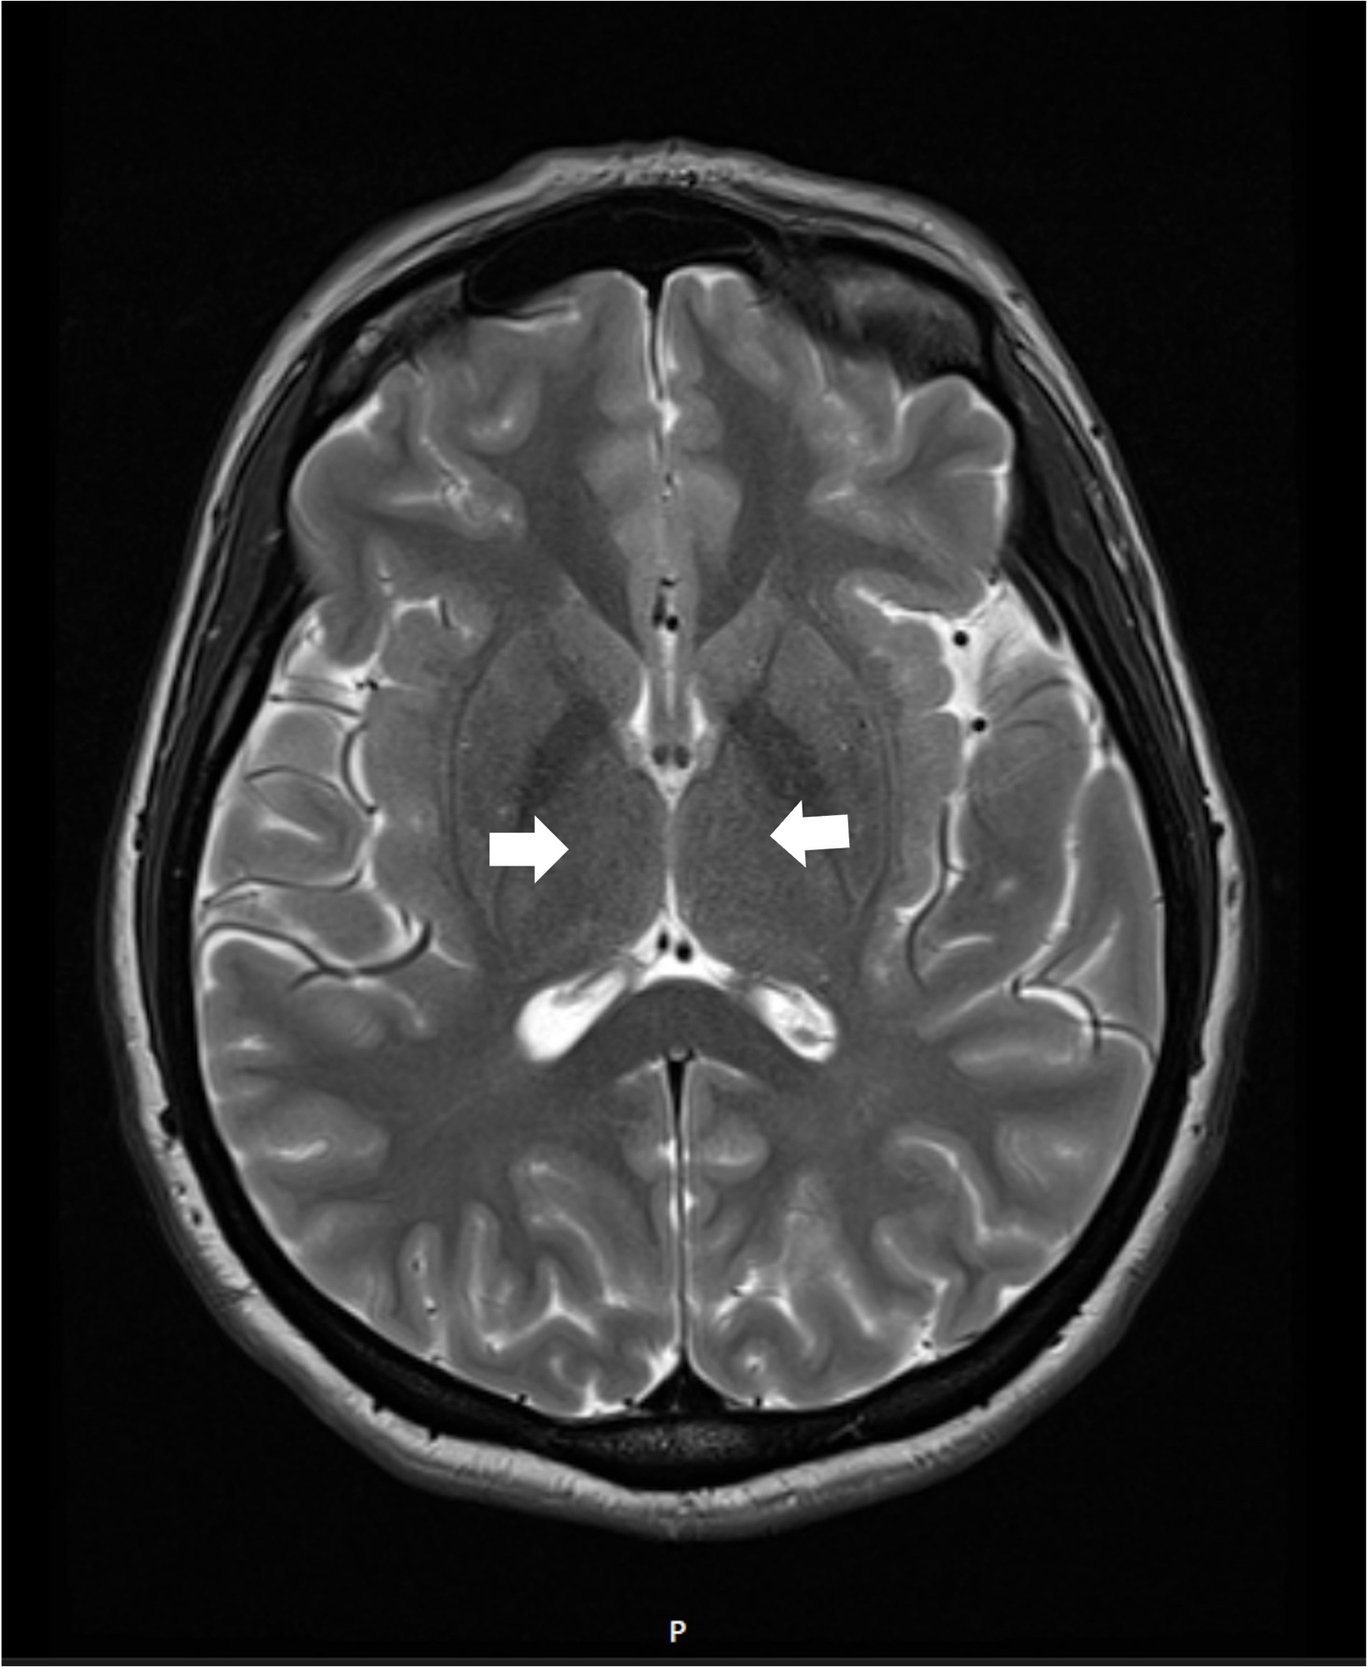

A comprehensive laboratory workup, including human immunodeficiency virus (HIV), Lyme disease serology, rapid plasma reagin (RPR) test, and viral hepatitis panel, was negative. The urine toxicology screen was positive for cannabinoids and amphetamines. Magnetic resonance imaging (MRI) of the brain demonstrated increased T2 signal intensity in the bilateral medial thalami with no involvement of the mamillary body (Figure 1). There was no evidence of optic neuritis, demyelinating lesions, meningeal enhancement, mass effect, or hemorrhage. MRI of the spine showed no active or chronic spinal cord lesions. Nerve conduction studies (NCS), along with serum testing for anti-ganglioside GM1 and anti-GQ1b antibodies, were normal. These tests were conducted to rule out atypical forms of demyelinating neuropathies in light of the patient’s hyporeflexia. Given the clinical presentation and imaging findings, a lumbar puncture (LP) was not performed, as there was no suspicion of infectious, demyelinating, or vascular pathology. The diagnosis of Wernicke’s encephalopathy was confirmed by a low whole blood thiamine level (7 nmol/L; reference range: 8–30 nmol/L), measured using liquid chromatography and mass spectrometry. Quantitative assays of other vitamins (B12, folate, Vitamin A, D, E and K) were within normal limits.